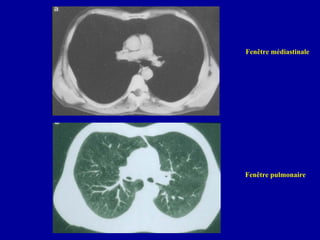

Fenêtre médiastinale

Fenêtre pulmonaire